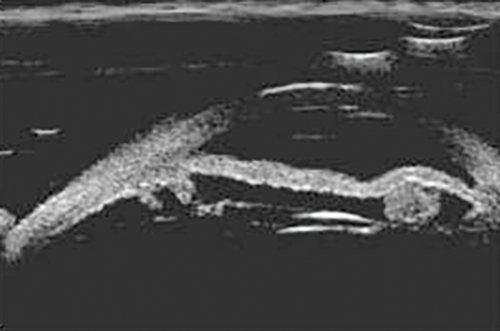

IOL haptic position / UGH syndrome

A patient who presented with persistent uveitis, raised pressure (glaucoma) and hyphaema (UGH syndrome) after cataract surgery appears to have an IOL haptic making direct contact with the posterior aspect of the iris (Figure 4). Unlike optical coherence tomography (OCTs), UBMs can more easily identify structures posterior to the iris. To facilitate the examination and direct the examiner to the appropriate area in the eye, it is useful for the clinician to indicate the position of the haptic / iris transillumination prior to the scan.